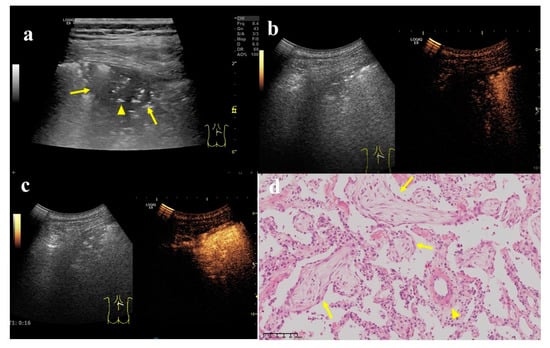

Figure 4. A 62-year-old female, who underwent total gastrectomy for gastric cancer 6 years ago and breast-conserving surgery for breast cancer 2 years ago, was coughing and expectorating for one month. (a) A wedge-shaped hypoechoic lesion (arrow) can be seen on the ultrasonic image of the right lung, with air bronchial sign inside (arrow head). Either angle between lesion border and thoracic wall was an acute angle. (b) After injection of contrast agent, the lesion began to enhance in 7 s, which was a uniform hyper-enhancement. The lung tissue began to enhance in 9 s, later than the lesion. (c) The enhancement of the lesion reached the peak in 16 s, and was a uniform enhancement. (d) An ultrasound-guided biopsy was performed. The pathological examination showed alveolar structure existed, the spacing was widened, and scattered lymphomonocytes could be seen in the focal alveolar cavity with cellulose exudation. Masson bodies (arrow) and small branch of pulmonary artery (arrow head) can be seen inside (×200). These findings conformed to the changes in organized pneumonia. After treatment with Medrol 8 mgqd for two months, the lesion became smaller and did not enlarge at the time of writing.